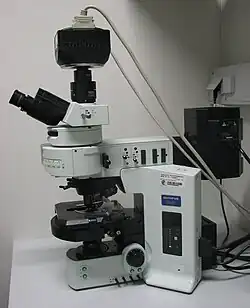

- Cellen die in het bloed aanwezig zijn kunnen gefenotypeerd worden op afgenomen bloed. Dit wordt vaak met speciale apparaten gedaan. De methode heet dan flowcytometrie, maar het werkt eigenlijk nog steeds met fluorescentiemicroscopie. Als zo'n apparaat de cellen ook kan scheiden, op basis van de kleur die aan de cel gebonden is, heet het een FACS-analyse. FACS staat voor 'Fluorescence Activated Cell Sorter'.